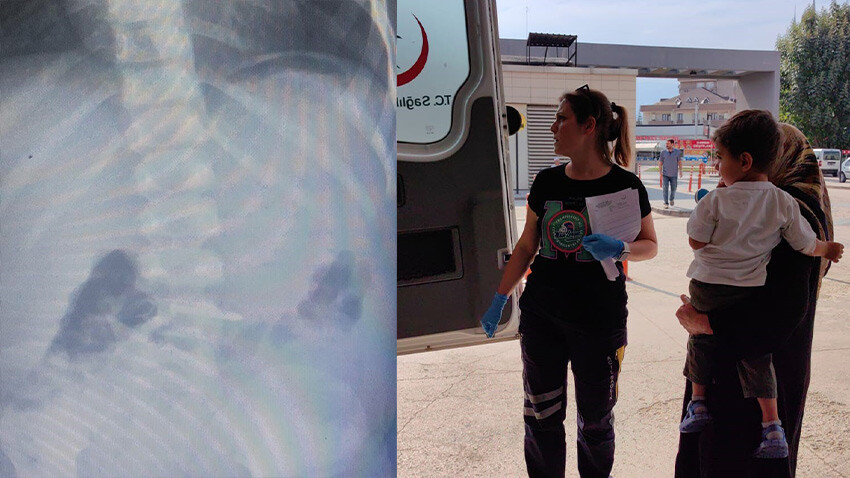

Bursa'da 2 yaşındaki bir çocuk evde oyun oynarken bulduğu çiviyi yuttu. Çivinin apar topar hastaneye götürülen çocuğun midesinde olduğu tespit edildi.

Olay, Mesudiye Mahallesi Sakin Sokak'ta meydana geldi. 2 yaşındaki Asil K., evde oynarken yerde bulduğu çiviyi ağzına atıp yuttu.

Olayı gören ailesi, küçük çocuğu hemen özel araçla İnegöl Devlet Hastanesi’ne götürdü. Yapılan tetkiklerde çivinin midesinde olduğu tespit edilen çocuk, ambulansla Bursa Yüksek İhtisas Eğitim ve Araştırma Hastanesi’ne sevk edildi. Polis olayla ilgili inceleme başlattı.